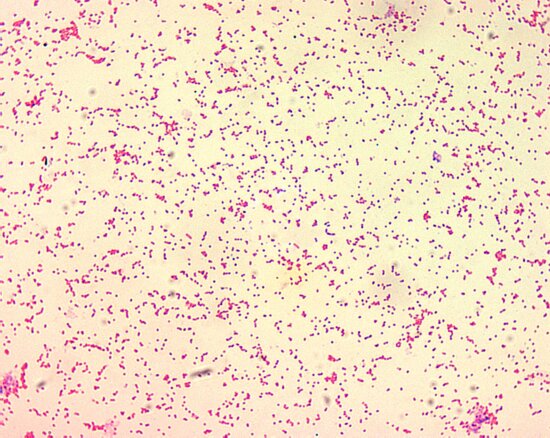

Causes of Bacteremia

Caused by Clostridium difficile, Pseudomonas, Staphylococcus, Hemophilus, E. coli, herpes, urinary tract infections, Streptococcus, peritonitis,